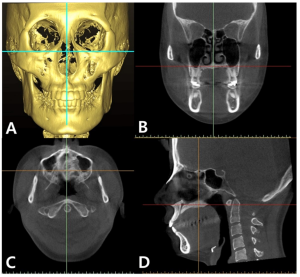

تصوير الجيوب الأنفية والأنف

يشير تصوير الجيوب الأنفية إلى مجموعة من إجراءات التصوير المستخدمة لفحص الجيوب الأنفية المحيطة بالأنف والوجه. تشمل هذه الإجراءات التصوير المقطعي المحوسب، والتصوير بالرنين المغناطيسي، والأشعة السينية. تُستخدم هذه الإجراءات لتشخيص وتقييم أمراض ومشاكل الجيوب الأنفية، مثل التهاب الجيوب الأنفية، والسلائل، والأورام، والتشوهات الهيكلية.